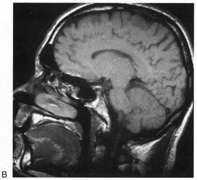

Fig. 15. Bilateral incomplete hemianopia. A 69-year-old man with decreased vision after prostate surgery. A. Fields show remaining central parafoveal vision with some sparing of inferior left quadrant. Note how the defect respects the vertical meridian. B. MRI shows bilateral medial occipital infarction, with sparing of the occipital poles, accounting for the macular-sparing bilaterally. (Courtesy of Dr. Lucia Vaina.)